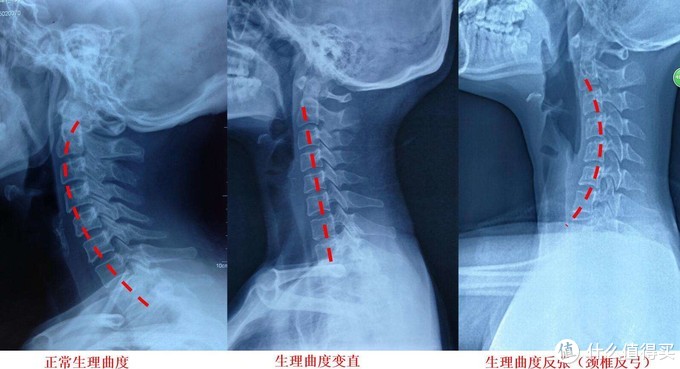

在医学上来说,颈椎指的是我们人体脊椎的第1~7节椎骨,并且包括了穿过其中的脊神经,以及颈椎周围的颈椎肌群。颈椎系统与我们的头部以及胸椎相连,如果只是承托头部而忽视了对颈部及肩部的承托,那么颈椎就会显现反曲压迫,是的颈椎肌群不能得到放松和修复,久而久之就会形成病理性的颈椎强直,并引发各种颈椎病及衍生病症。而如果只承托颈部,而忽视了对头部及肩部的承托,那么就会导致颈椎过曲,照样会引发问题。